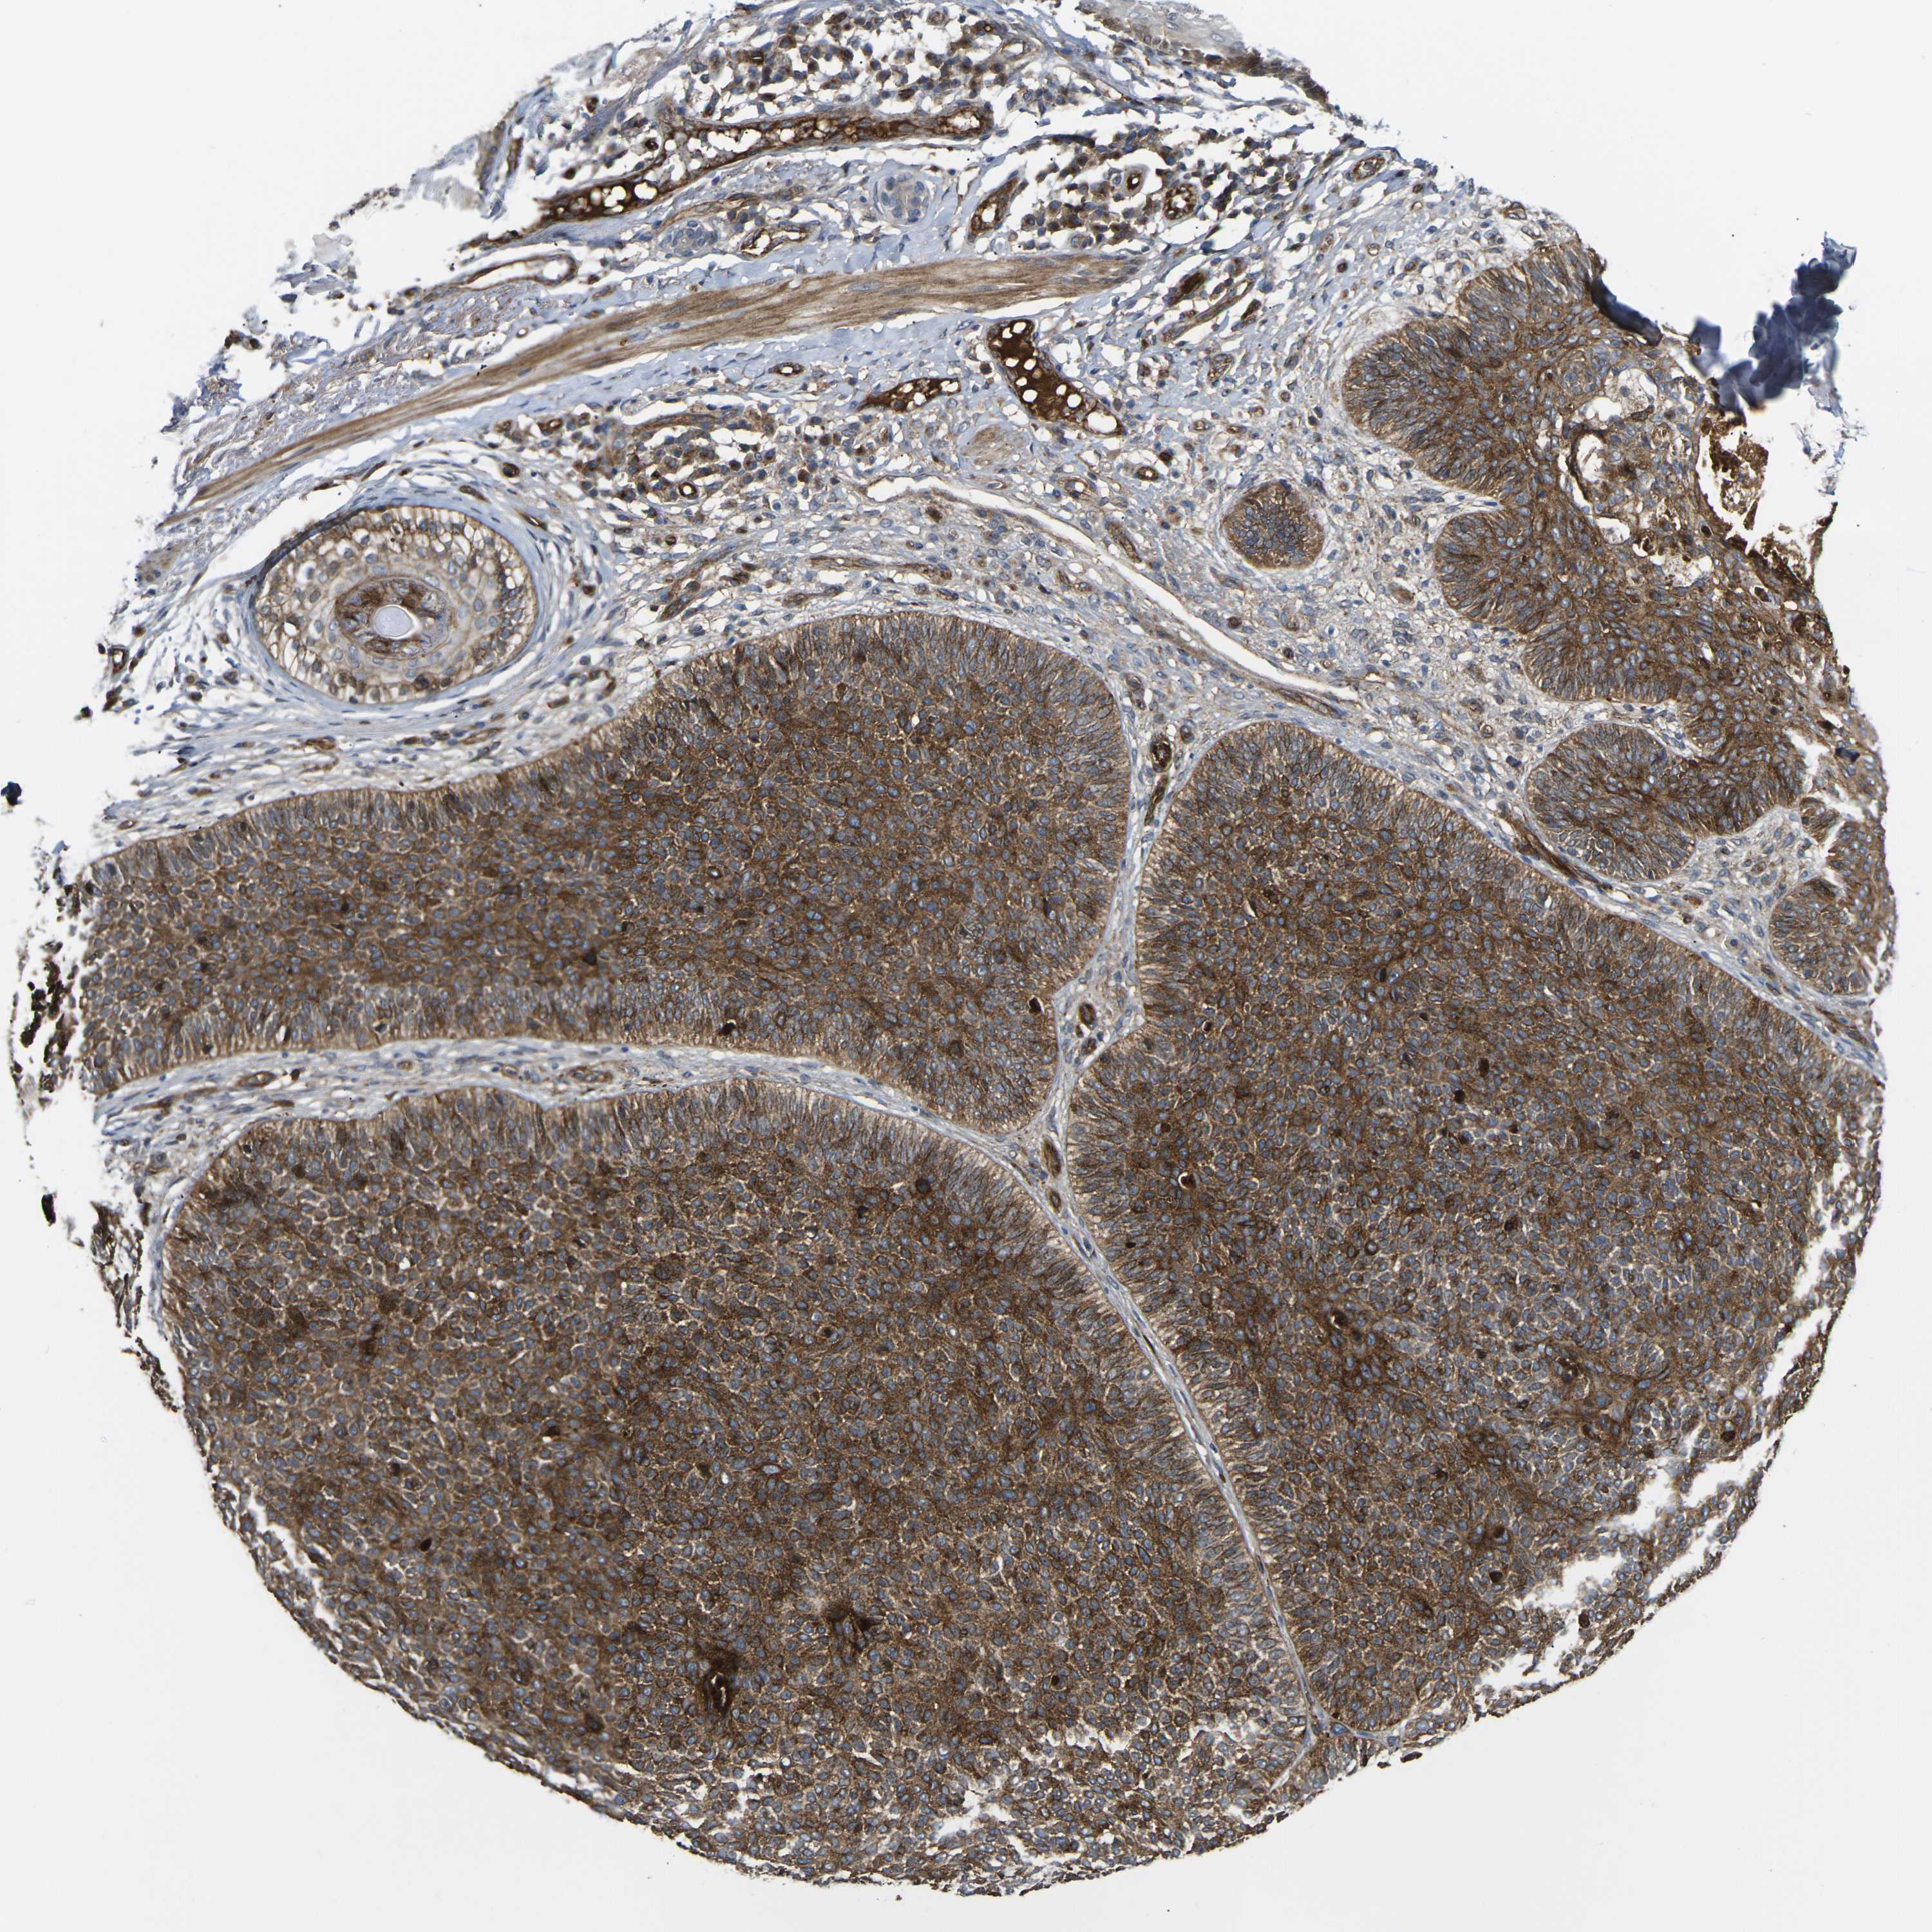

CANCER SKIN CANCER Show tissue menu

SKIN CANCER - Protein expressioni

A mouse-over function shows sample information and annotation data. Click on an image to view it in a full screen mode. Samples can be filtered based on level of antibody staining by selecting one or several of the following categories: high, medium, low and not detected. The assay and annotation is described here.

Antibody stainingi

Antibody staining in the annotated cell types in the current human tissue is reported as not detected, low, medium, or high, based on conventional immunohistochemistry profiling in selected tissues. This score is based on the combination of the staining intensity and fraction of stained cells.

Each image is clickable and will lead to virtual microscopy that enables deeper exploration of all samples and also displays staining intensity scores, fraction scores and subcellular localization as well as patient and tissue information for each sample.

Antibody HPA001490

Antibody HPA013616

Staining

High

Medium

Low

Not detected

Intensity

Strong

Moderate

Weak

Negative

Quantity

>75%

75%-25%

<25%

None

Location

Nuclear

Cytoplasmic/membranous

Cytoplasmic/membranous,nuclear

Squamous cell carcinoma, NOS

Basal cell carcinoma